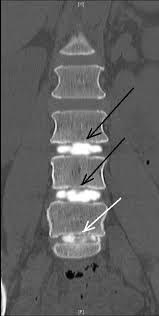

Your doctor will use an imaging technique (fluoroscopy) that enables him or her to watch as the needle enters your body. Fluoroscopy allows more precise and safer placement of the needle into the center of the disk to be examined. A contrast dye is then injected into the disk, and an X-ray or CT scan is taken to see if the dye spreads.

If the dye stays in the center of the disk, the disk is normal. If the dye spreads outside the center of the disk, the disk has undergone some wear-and-tear change. These changes may or may not be the cause of your pain.